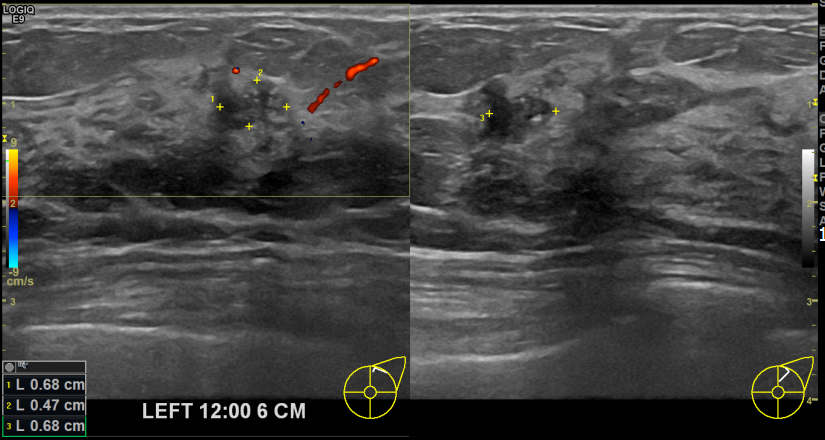

아산유외과개원후 723번째 유방암진단

상기환자 유방암가족력으로 본원에서 꾸준히 경과관찰하시던분으로 30대 여성분으로 좌측에 석회증가와 커진혹 있어 조직검사 후 유방암진단되었습니다.